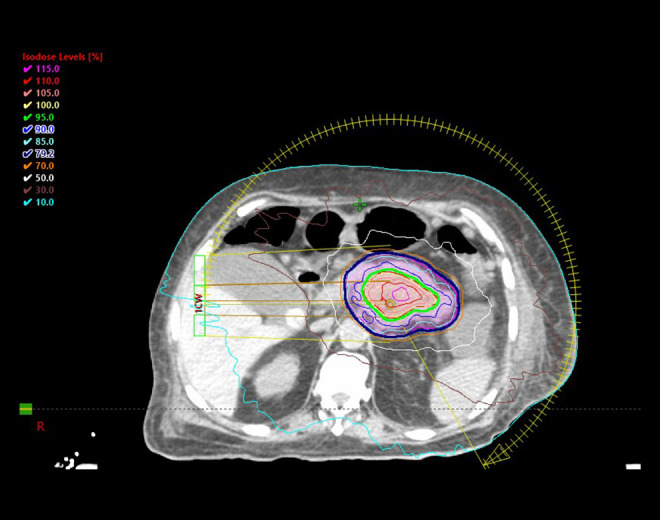

BACKGROUND Treatment of metastatic vasoactive intestinal peptide tumors (VIPoma) is challenging and requires a careful multidisciplinary approach to achieve optimal disease control. We present a case of metastatic VIPoma with recurring episodes of life-threatening diarrhea necessitating multiple intensive care unit (ICU) admissions. CASE REPORT A 54-year-old man presented with severe watery diarrhea and metabolic acidosis with MRI showing a necrotic pancreatic body mass, and multiple liver lesions. Histopathologic and biochemical findings were consistent with VIPoma. Due to the multifocal liver lesions, he was deemed unsuitable for curative surgical intervention, shifting focus to other therapies. Initial treatments over 7 months included octreotide, transarterial chemoembolization, yttrium-90 radioembolization, and systemic therapy with everolimus, with decreases in serum vasoactive intestinal peptide (VIP) levels from a peak of 3180 pg/mL to undetectable levels corresponding to temporary relief of diarrhea. However, the temporary relief was followed by a rapid increase in VIP levels into the 200s and 300s and recurrence of 3-11 liters of diarrhea per day. He had multiple ICU admissions due to severe diarrhea/hypovolemic shock until he was treated with stereotactic body radiation therapy (SBRT). SBRT of the pancreatic site immediately yielded long-term hemodynamic stability, prevented further ICU admissions, and enabled the patient to receive debulking surgery. CONCLUSIONS Although radiation is not typically a primary treatment modality for VIPoma, in this case, the high dose per fraction delivered with stereotactic technique to a pancreatic mass played a crucial role in alleviating his catastrophic volume loss through intravenous octreotide-refractory diarrhea, making the patient a suitable candidate for debulking surgery. This case highlights the importance of considering all available treatment options, even those not traditionally employed, when managing complex cases with refractory symptoms.